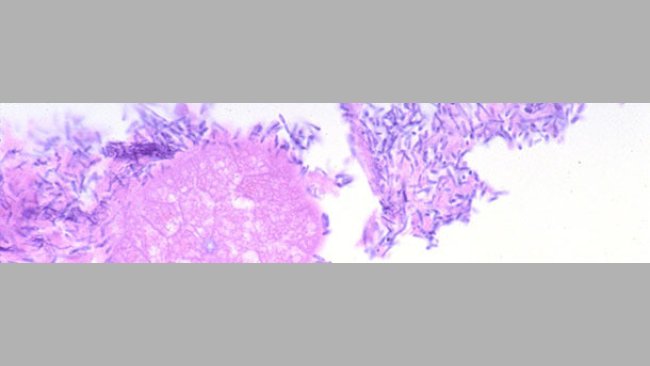

Klinischer Fall: Probleme mit Salmonellose und PCV2-assoziierten Erkrankungen bei Aufzucht und Mastbeginn

Wir wurden gebeten, einen Mastbetrieb zu besuchen, in dem 7 Wochen alte Ferkel nach dem Absetzen an Meningitis und Diarrhö erkrankt waren. Die Mortalitätsrate lag 3 Wochen nach dem Absetzen bei 5%.